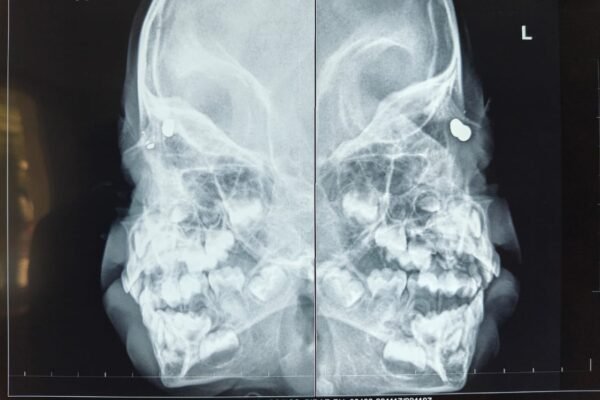

Sankara Eye Hospital, Hyderabad, Successfully Treats Rare Orbital Air Gun Pellet Eye Injury in Three-Year-Old Child

Hyderabad, December 21, 2025: Doctors at Sankara Eye Hospital, Hyderabad, successfully treated a three-year-old boy who sustained a rare orbital injury after an accidental air gun pellet entered his face and migrated close to the eye. The child was referred to Sankara Eye Hospital after multiple initial consultations failed to detect the seriousness of the…